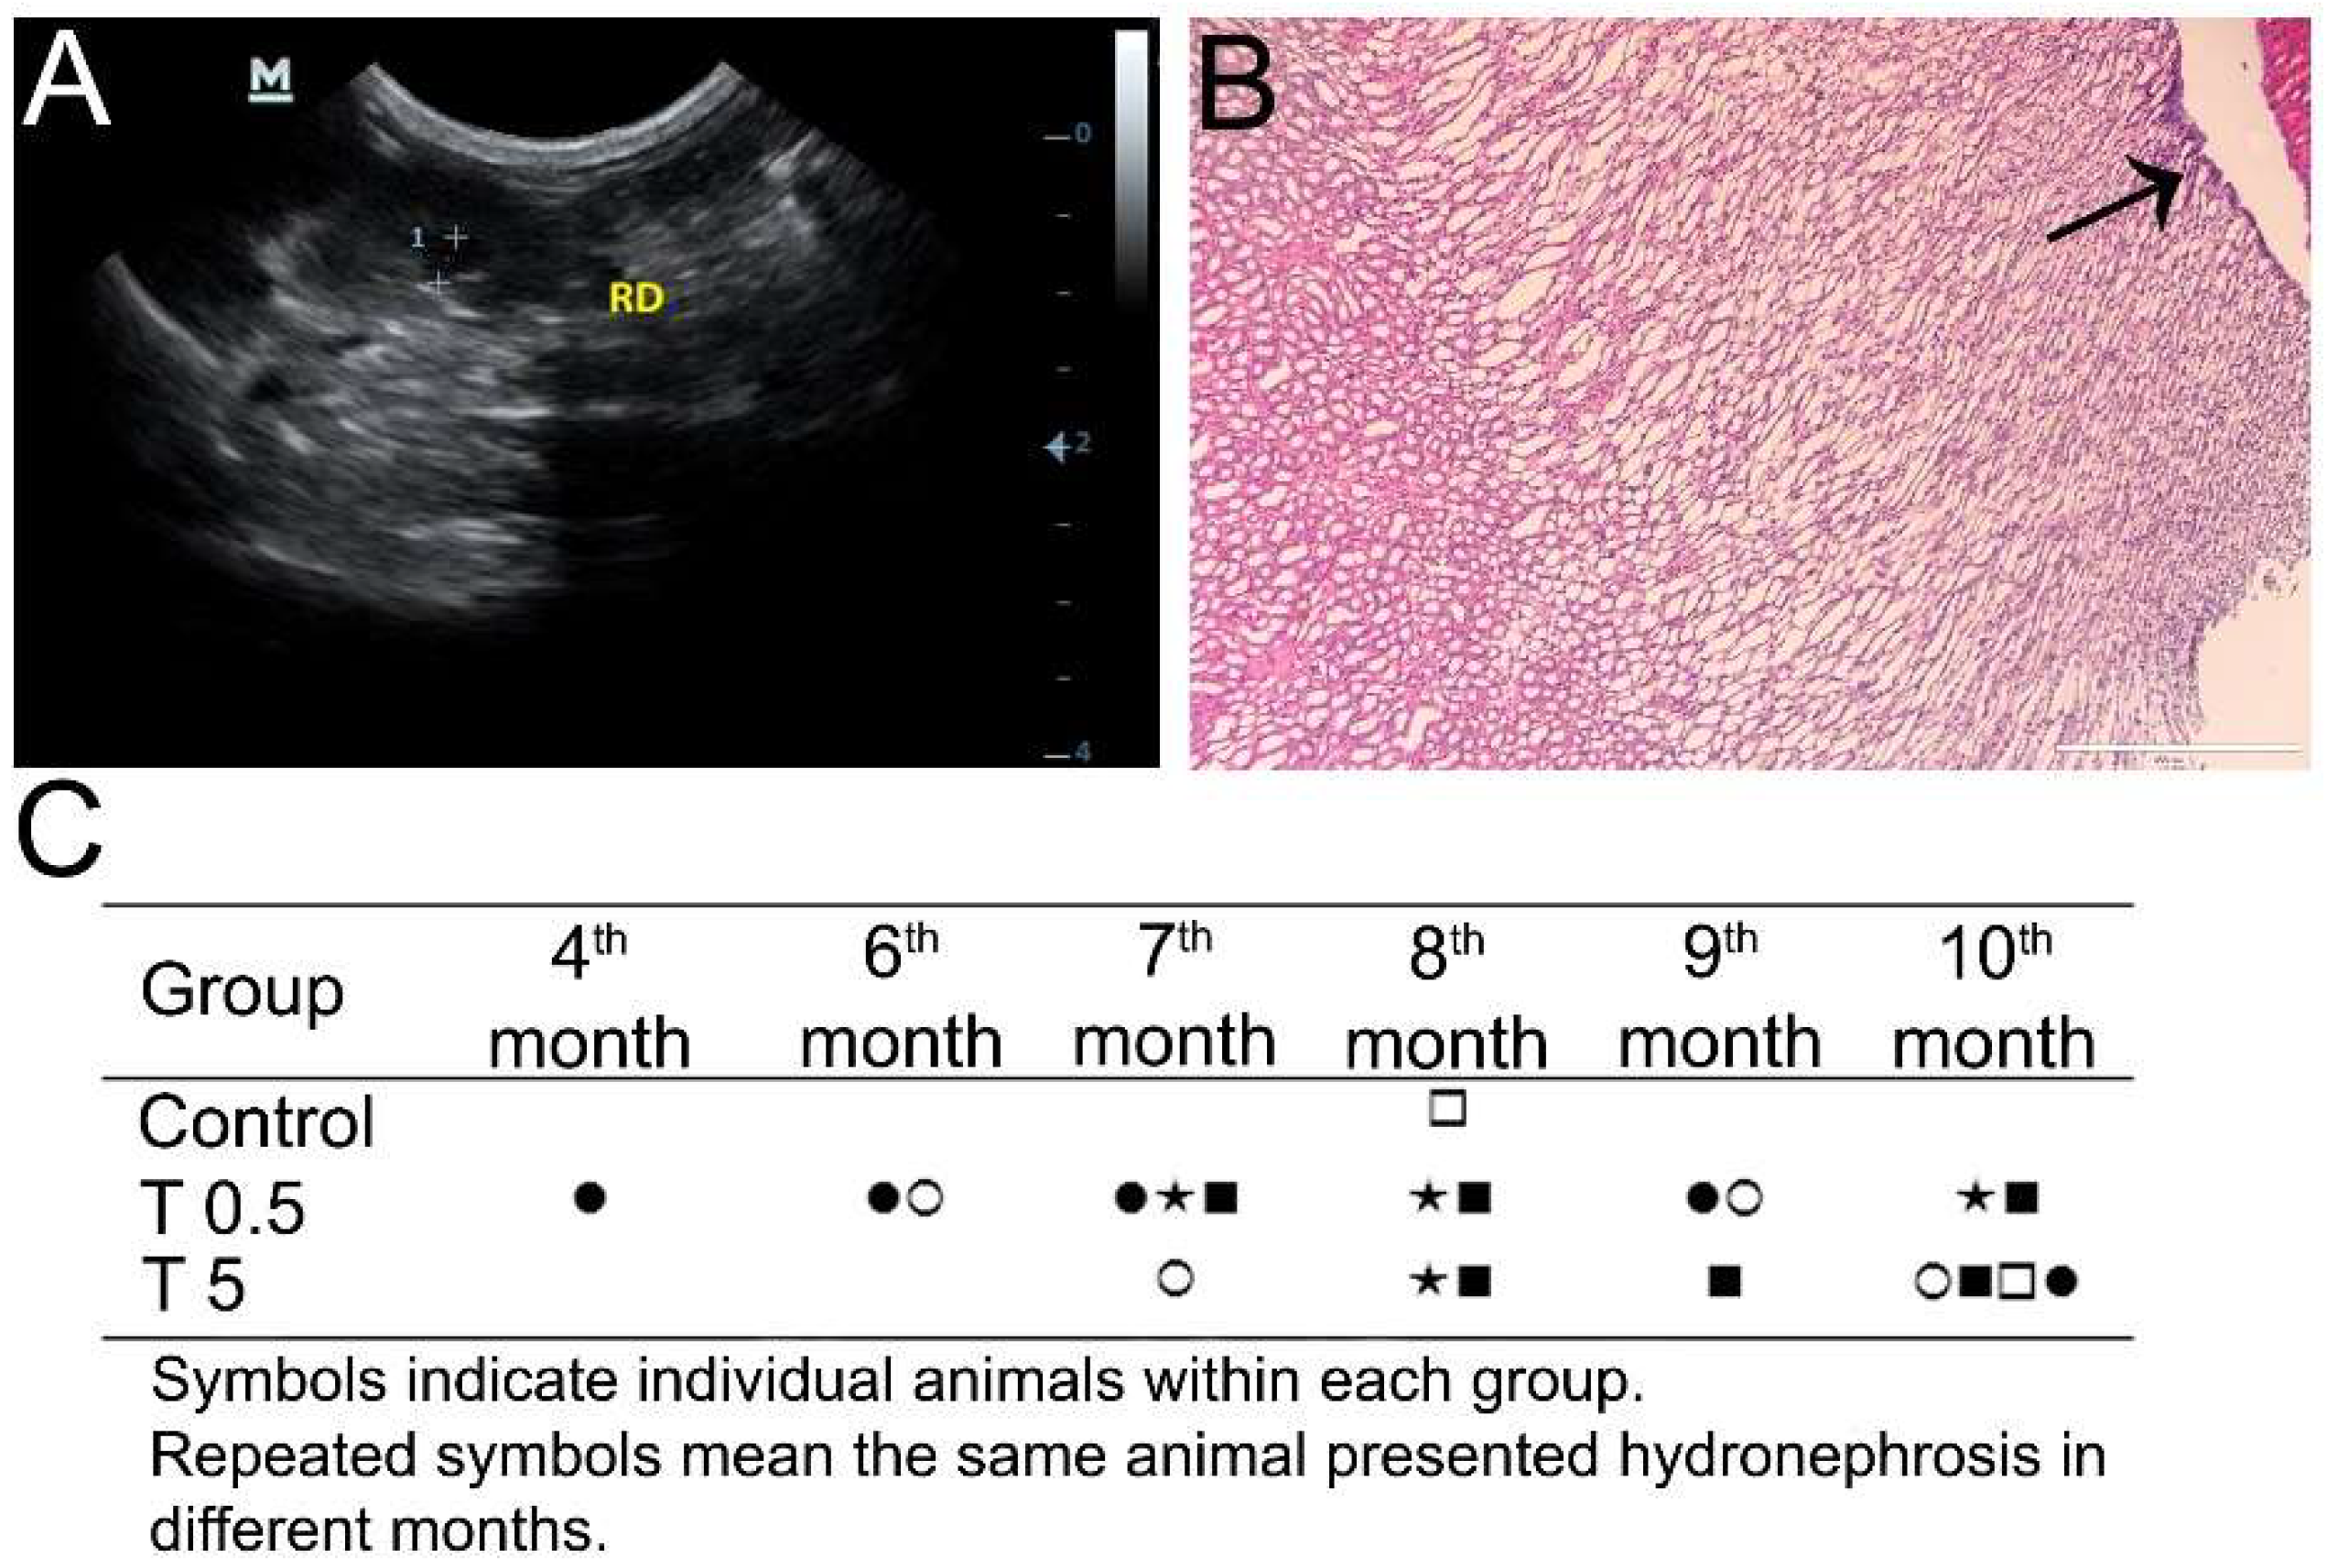

2.4. Ultrasound Analysis

3.3. Ultrasonography Analysis